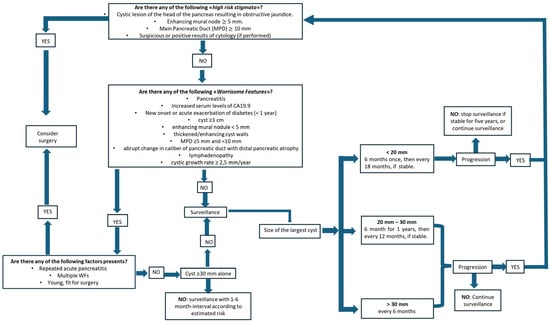

Figure 6 shows a clear management of IPMN answering some questions as described below:

Figure 6.

Algorithm for management of IPMN.

- Are any “high-risk stigmata” of malignancy present?

- ○

- If the answer is yes, the management direction aims towards surgery.

- ○

- If the answer is no, as often happens, we focus on the second question:

- Are any “worrisome features” present?

- ○

- If there aren’t any worrisome features, surveillance is required and it will depend on the size of the cyst.

- ○

- If some worrisome features are present, we focus of the third question:

- Are there any of the following factors present: repeated acute pancreatitis, multiple WFs, patient young and fit for surgery?

- ○

- If the answer is yes, consider surgery.

- ○

- If the answer is no, surveillance is required.

It is, however, important to note that the role of cyst size as a standalone criterion remains controversial. Some studies have downplayed the significance of this parameter, observing that in several surgical series of resected IPMNs, a cyst size ≥ 3 cm showed a positive predictive value (PPV) for malignancy of only 27–33% [47].

Other studies have validated the safety of observation of BD-IPMN measuring <4 cm in the absence of other risk factors [48,49]. Cyst size alone should be considered an appropriate indication for surgery, while if multiple risk factors are present, the sensitivity of size to detect malignancy increases [50].

In his meta-analysis, Marchegiani demonstrated that the presence of mural nodules (MNs) was the strongest independent predictor of invasive cancer and high-grade dysplasia (HGD) for all type of IPMNs (with the exception of HGD in BD-IPMNs). Also, the mural nodule size could be a parameter used to predict the malignancy of IP-MNs [51].

Overall, the primary limitation of the Kyoto guidelines is that many of the supporting studies lack a high and robust level of recommendation. Consequently, although these guidelines synthesize the available evidence, their practical application remains a subject of debate, particularly regarding the surveillance of non-resected BD-IPMNs [52].

Ultimately, the most significant achievement of the Kyoto guidelines has been to highlight the necessity of a management algorithm tailored specifically to the individual patient [53].